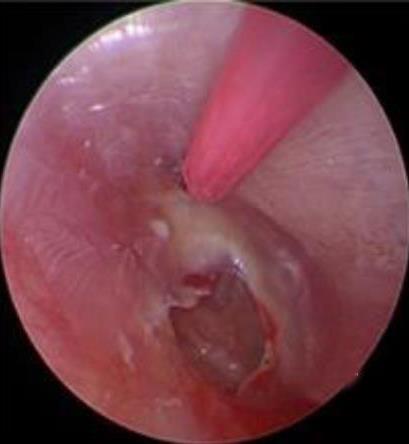

摘要:目的 分析医用生物蛋白胶应用于耳内镜下鼓膜修补术的临床疗效。方法 回顾性分析2022年10月-2023年10月该院收治的60例单纯鼓膜穿孔患者的临床资料,根据手术方法不同,将患者分为研究组和对照组,各30例。研究组术中使用医用生物蛋白胶粘合残余鼓膜和修补材料;对照组术中采用明胶海绵覆盖修补鼓膜。观察两组患者术后的鼓膜愈合情况(鼓膜愈合率、愈合时间、干耳时间和外耳道上下径)和并发症发生情况;于手术前后,采用纯音测听法(500、1 000、2 000、4 000 Hz),测量两组患者气导阈值,观察听力改善程度;采用视觉模拟评分法(VAS)评分,评估患者术后疼痛程度。结果 两组患者术后鼓膜愈合率、愈合时间、外耳道上下径和并发症发生率比较,差异均无统计学意义(P > 0.05)。研究组术后平均气导听阈明显低于对照组,差异有统计学意义(P < 0.05)。研究组术后干耳时间短于对照组,术后第1天疼痛VAS评分明显低于对照组,差异均有统计学意义(P < 0.05)。结论 医用生物蛋白胶应用于耳内镜下鼓膜修补术,可有效地降低气导听阈,缩短干耳时间,减轻患者疼痛,且不增加并发症发生率,值得临床推广应用。